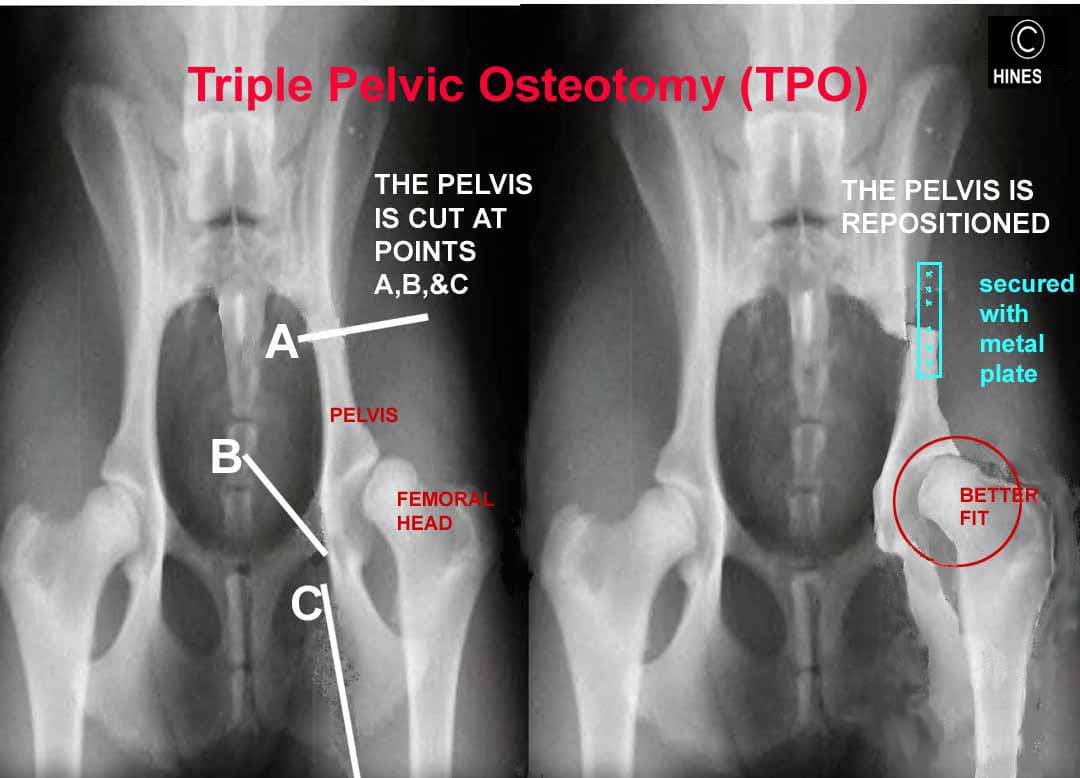

Double Triple Pelvic Osteotomy DPO TPO plate

Hip dysplasia Fitzpatrick Referrals

Triple Pelvic Osteotomy Orthopaedics WA

When Your Dog Faces Hip Dysplasia Ron Hines Vetspace 2nd Chance The Animal Health Website

The Veterinary Nurse Surgical treatment options for hip dysplasia

Product Name: Tpo hip surgery dealsAnimal Surgical Center of Michigan Veterinarian in Flint MI deals, Triple Pelvic Osteotomy Orthopaedics WA deals, Triple Pelvic Osteotomy Southwest Veterinary Surgical Service deals, Animal Surgical Center of Michigan Veterinarian in Flint MI deals, Animal Surgical Center of Michigan Veterinarian in Flint MI deals, Animal Surgical Center of Michigan Veterinarian in Flint MI deals, a Pelvic radiograph of a female performed one year after TPO. Surgery. Download Scientific Diagram deals, Double Triple Pelvic Osteotomy DPO TPO plate deals, Vet Orthopaedic Referrals Ireland fractures spine cruciate TPLO hip deals, Double Triple Pelvic Osteotomy DPO TPO plate deals, hip dysplasia triple pelvic osteotomy tpo jps Orthopaedic Referral Service fracture spine clinic joint spinal surgery arthroscopy N Ireland dog and cat veterinary specialists specialist vets deals, hip dysplasia triple pelvic osteotomy tpo jps Orthopaedic Referral Service fracture spine clinic joint spinal surgery arthroscopy N Ireland dog and cat veterinary specialists specialist vets deals, THR DPO FHO TPLO and TTA How to Talk to Your Veterinarian About Orthopedic Surgery The Animal Medical Center deals, Hip Dysplasia Oakdale Veterinary Group deals, Hip Dysplasia Hip Conditions in Dogs Surgery Costs deals, hip dysplasia triple pelvic osteotomy tpo jps Orthopaedic Referral Service fracture spine clinic joint spinal surgery arthroscopy N Ireland dog and cat veterinary specialists specialist vets deals, Animal Surgical Center of Michigan Veterinarian in Flint MI deals, Double Triple Pelvic Osteotomy DPO TPO plate deals, Vet Orthopaedic Referrals Ireland fractures spine cruciate TPLO hip deals, Total Hip Replacement A Complete Information Guide by Russell Kalis DVM DACVS SA AVES deals, Hip Dysplasia in dogs and cats Long Beach Animal Hospital deals, Hip dysplasia Fitzpatrick Referrals deals, Frontiers The Use of Sixty Degree Rotation of the Acetabulum for Treatment of Dogs With Canine Hip Dysplasia. A Short Case Series deals, THR DPO FHO TPLO and TTA How to Talk to Your Veterinarian About Orthopedic Surgery The Animal Medical Center deals, Double Triple Pelvic Osteotomy DPO TPO plate deals, Hip dysplasia Fitzpatrick Referrals deals, Triple Pelvic Osteotomy Orthopaedics WA deals, When Your Dog Faces Hip Dysplasia Ron Hines Vetspace 2nd Chance The Animal Health Website deals, The Veterinary Nurse Surgical treatment options for hip dysplasia deals, Hip dysplasia when do we consider surgery deals, Tpo shop dog surgery deals, Vet Orthopaedic Referrals Ireland fractures spine cruciate TPLO hip deals, Royal Orthopaedic Hospital Triple Pelvic Osteotomy TPO deals, Hip dysplasia when do we consider surgery Vet Times deals, Femoral Head and Neck Excision Arthroplasty Arizona Canine Orthopedics Sports Medicine deals.